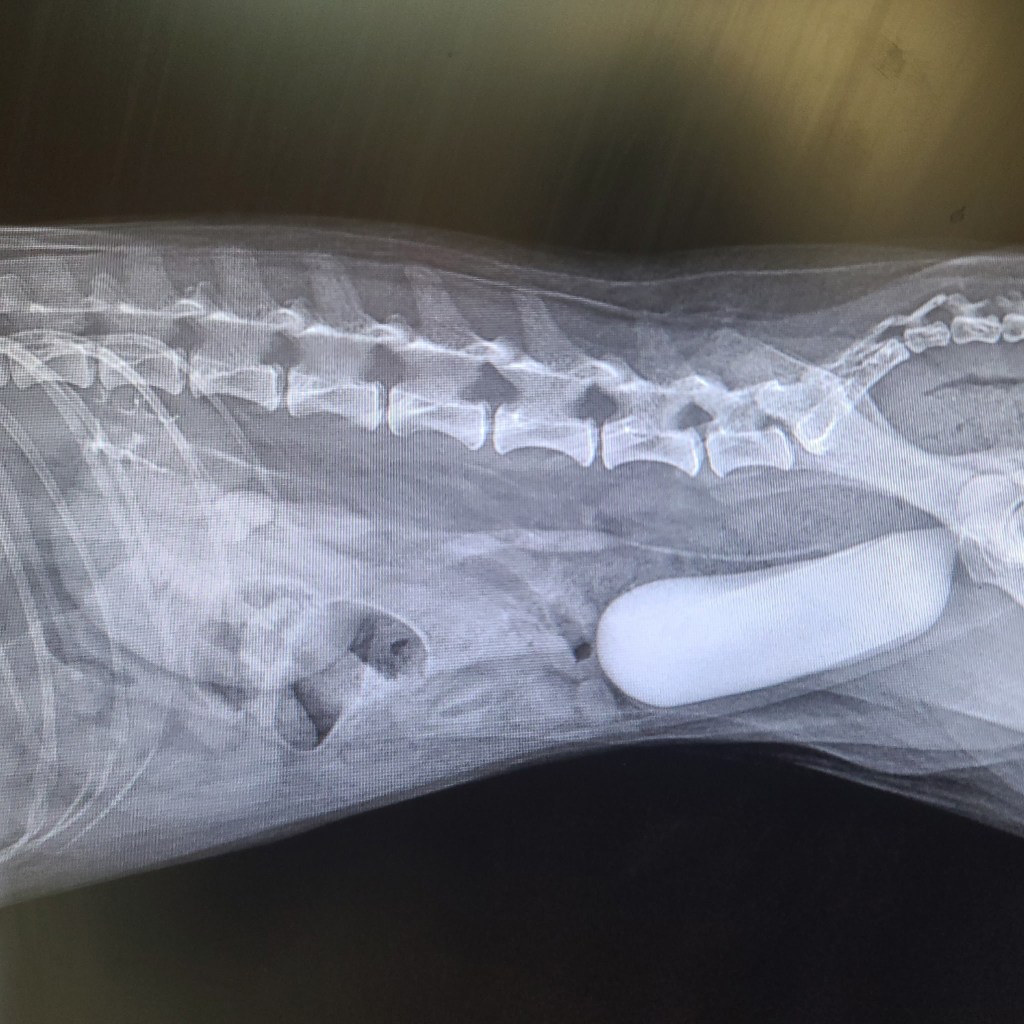

Radiography (X‑rays) is a safe, noninvasive way for us to look inside your pet’s body and see structures we can’t evaluate on a physical exam alone. In small animals, X‑rays are commonly used to assess bones and joints for fractures, arthritis, or developmental problems; to examine the chest for heart enlargement, fluid, or lung disease; and to evaluate the abdomen for foreign objects, tumors, organ enlargement, or blockages. Digital radiographs can be taken quickly and with minimal stress, allowing us to make faster, more accurate diagnoses and start appropriate treatment sooner. In many cases, radiography helps us avoid more invasive procedures and provides an essential first step in planning surgery or advanced care for your pet